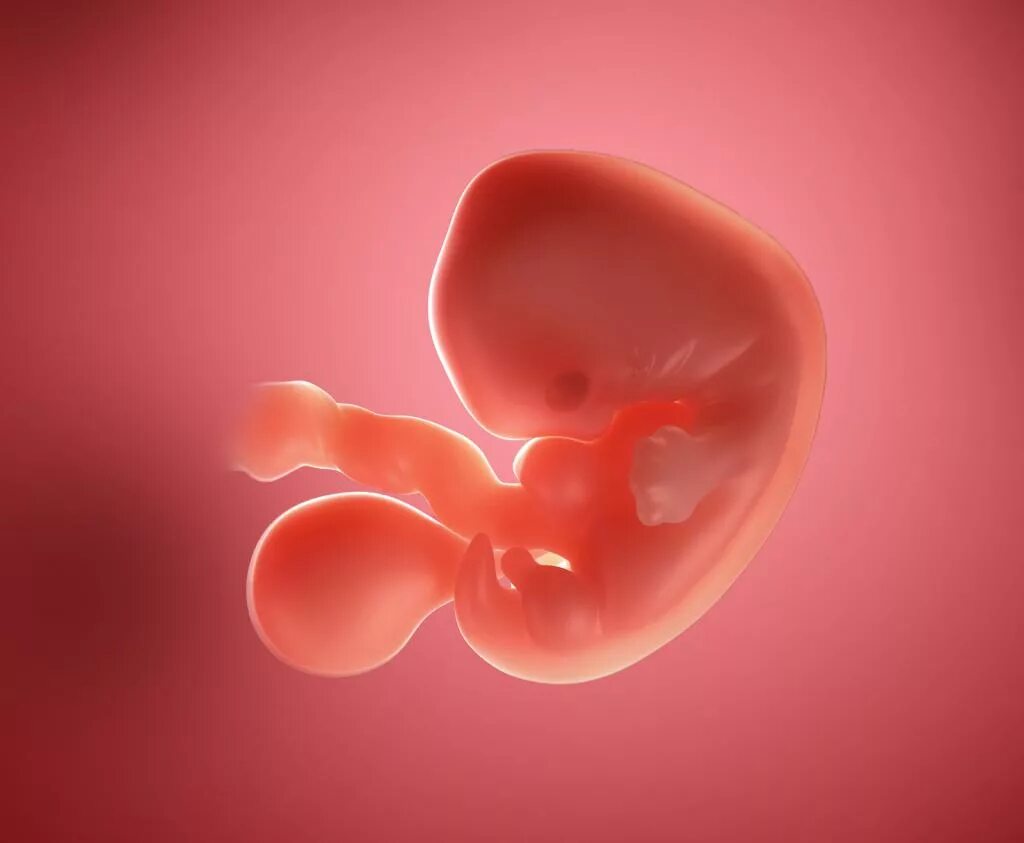

6 недель беременности как выглядит эмбрион